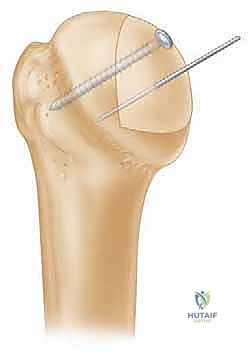

الخطوة الخامسة: تثبيت الطعم العظمي (Fixation)

يتم تنظيف موقع آفة هيل ساكس من الأنسجة الليفية للوصول إلى عظم حي ينزف، مما يحفز عملية الالتئام. بعد ذلك، يتم إدخال الطعم العظمي المُشكل في مكانه.

يستخدم الدكتور هطيف براغي طبية خاصة (غالباً براغي التيتانيوم المجوفة أو البراغي القابلة للامتصاص) لتثبيت الطعم بقوة فائقة في رأس عظم العضد. يتم غرس رؤوس البراغي تحت مستوى سطح الغضروف لضمان عدم احتكاكها بالجوف الحقاني أثناء حركة الكتف.